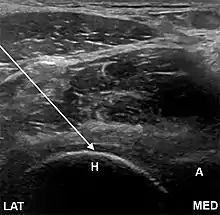

- The anterolateral approach, with the ultrasound probe oriented axially and the femoral head and acetabular rim in view. This often shortens the distance from needle skin entry to joint compared to the longitudinal approach making it a useful approach in larger patients. The introduced needle remains lateral to the femoral neurovascular bundle, and the needle is advanced until its tip rests on the femoral head.

- A low-frequency curvilinear probe (5-2 MHz), coated with a glue sterile dressing table, is put in a transverse plane parallel to the inguinal ligament and utilized to recognize the femoral artery and vein over the hyperechoic femoral head. The probe is then transferred laterally to just over the hyper-echoic femoral head and rotated into an oblique sagittal place so the probe mark is targeted towards the umbilicus.